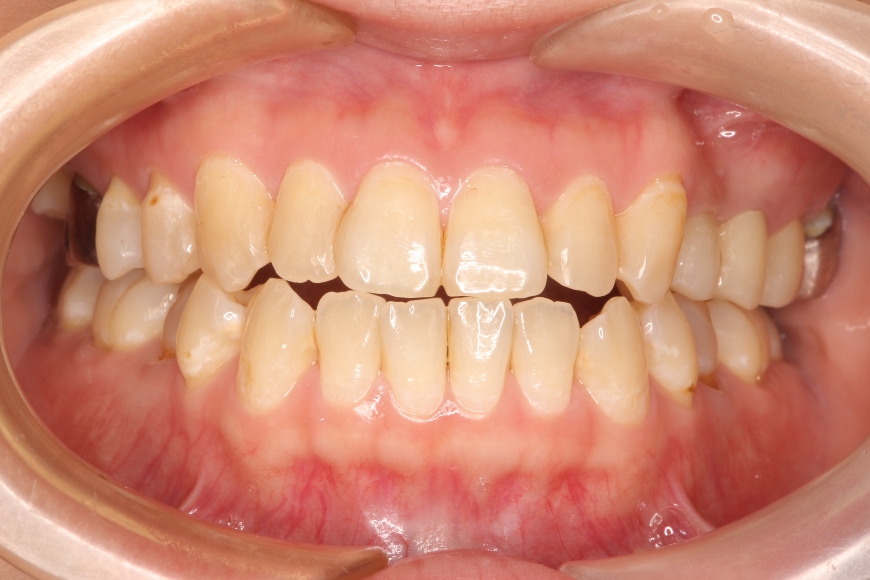

8歳男児 歯並びをきれいにしたい(保護者より)

治療前

治療後

治療内容 「がたがたの歯を治したい」と保護者と共に来院されました。

スペース不足による叢生(ガタガタの状態)と、前歯の見栄えが悪い状態でした。

床矯正装置にて2年程度歯列拡大を行い、永久歯の萌出誘導を行い、きれいな歯並びを獲得しました。

治療期間・回数 治療期間:約3年

通院回数:25~30回程度(成長段階に合わせた調整含む)

242,000

(調整料込、治療時の金額であり、時期や手法により異なる場合があります。)

副作用・リスク ・顎の成長後に後戻りが起こる可能性があります。

・予定より治療期間が長くなることがあります。

・2期治療(大人の矯正)に移行することがあります。